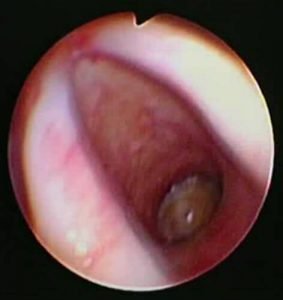

Contrast enhanced computed tomography (CECT) of neck and thorax reported intraluminal mildly enhancing polypoidal mass lesion measuring 2.58 x 1.54 x 1.51 cm (Cc X AP X Tr) in the upper trachea at the level of C6, C7 vertebral body. Significant luminal compromise was noted at the level of the mass lesion. Rest of the lung parenchyma was unremarkable. Flexible bronchoscopy examination revealed a large polyploidal growth approximately 3 cm from the vocal cords. The growth was moving with respiration and causing critical airway narrowing at the upper trachea (approximately 80%).

Diagnostic Flexible bronchoscopy Examination